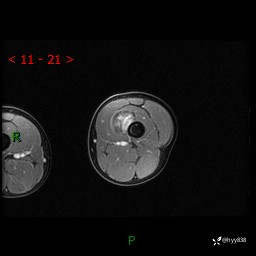

左大腿MRI平扫+增强